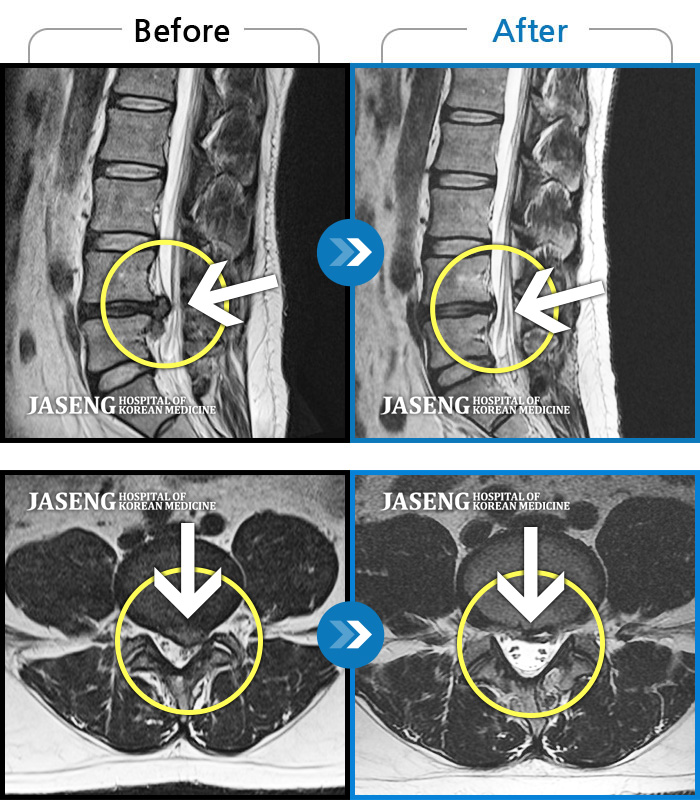

허리 골반 통증이 있고 다리가 저리고 아파 걷기가 힘들다.

2025.02.10 ~ 2025.09.13